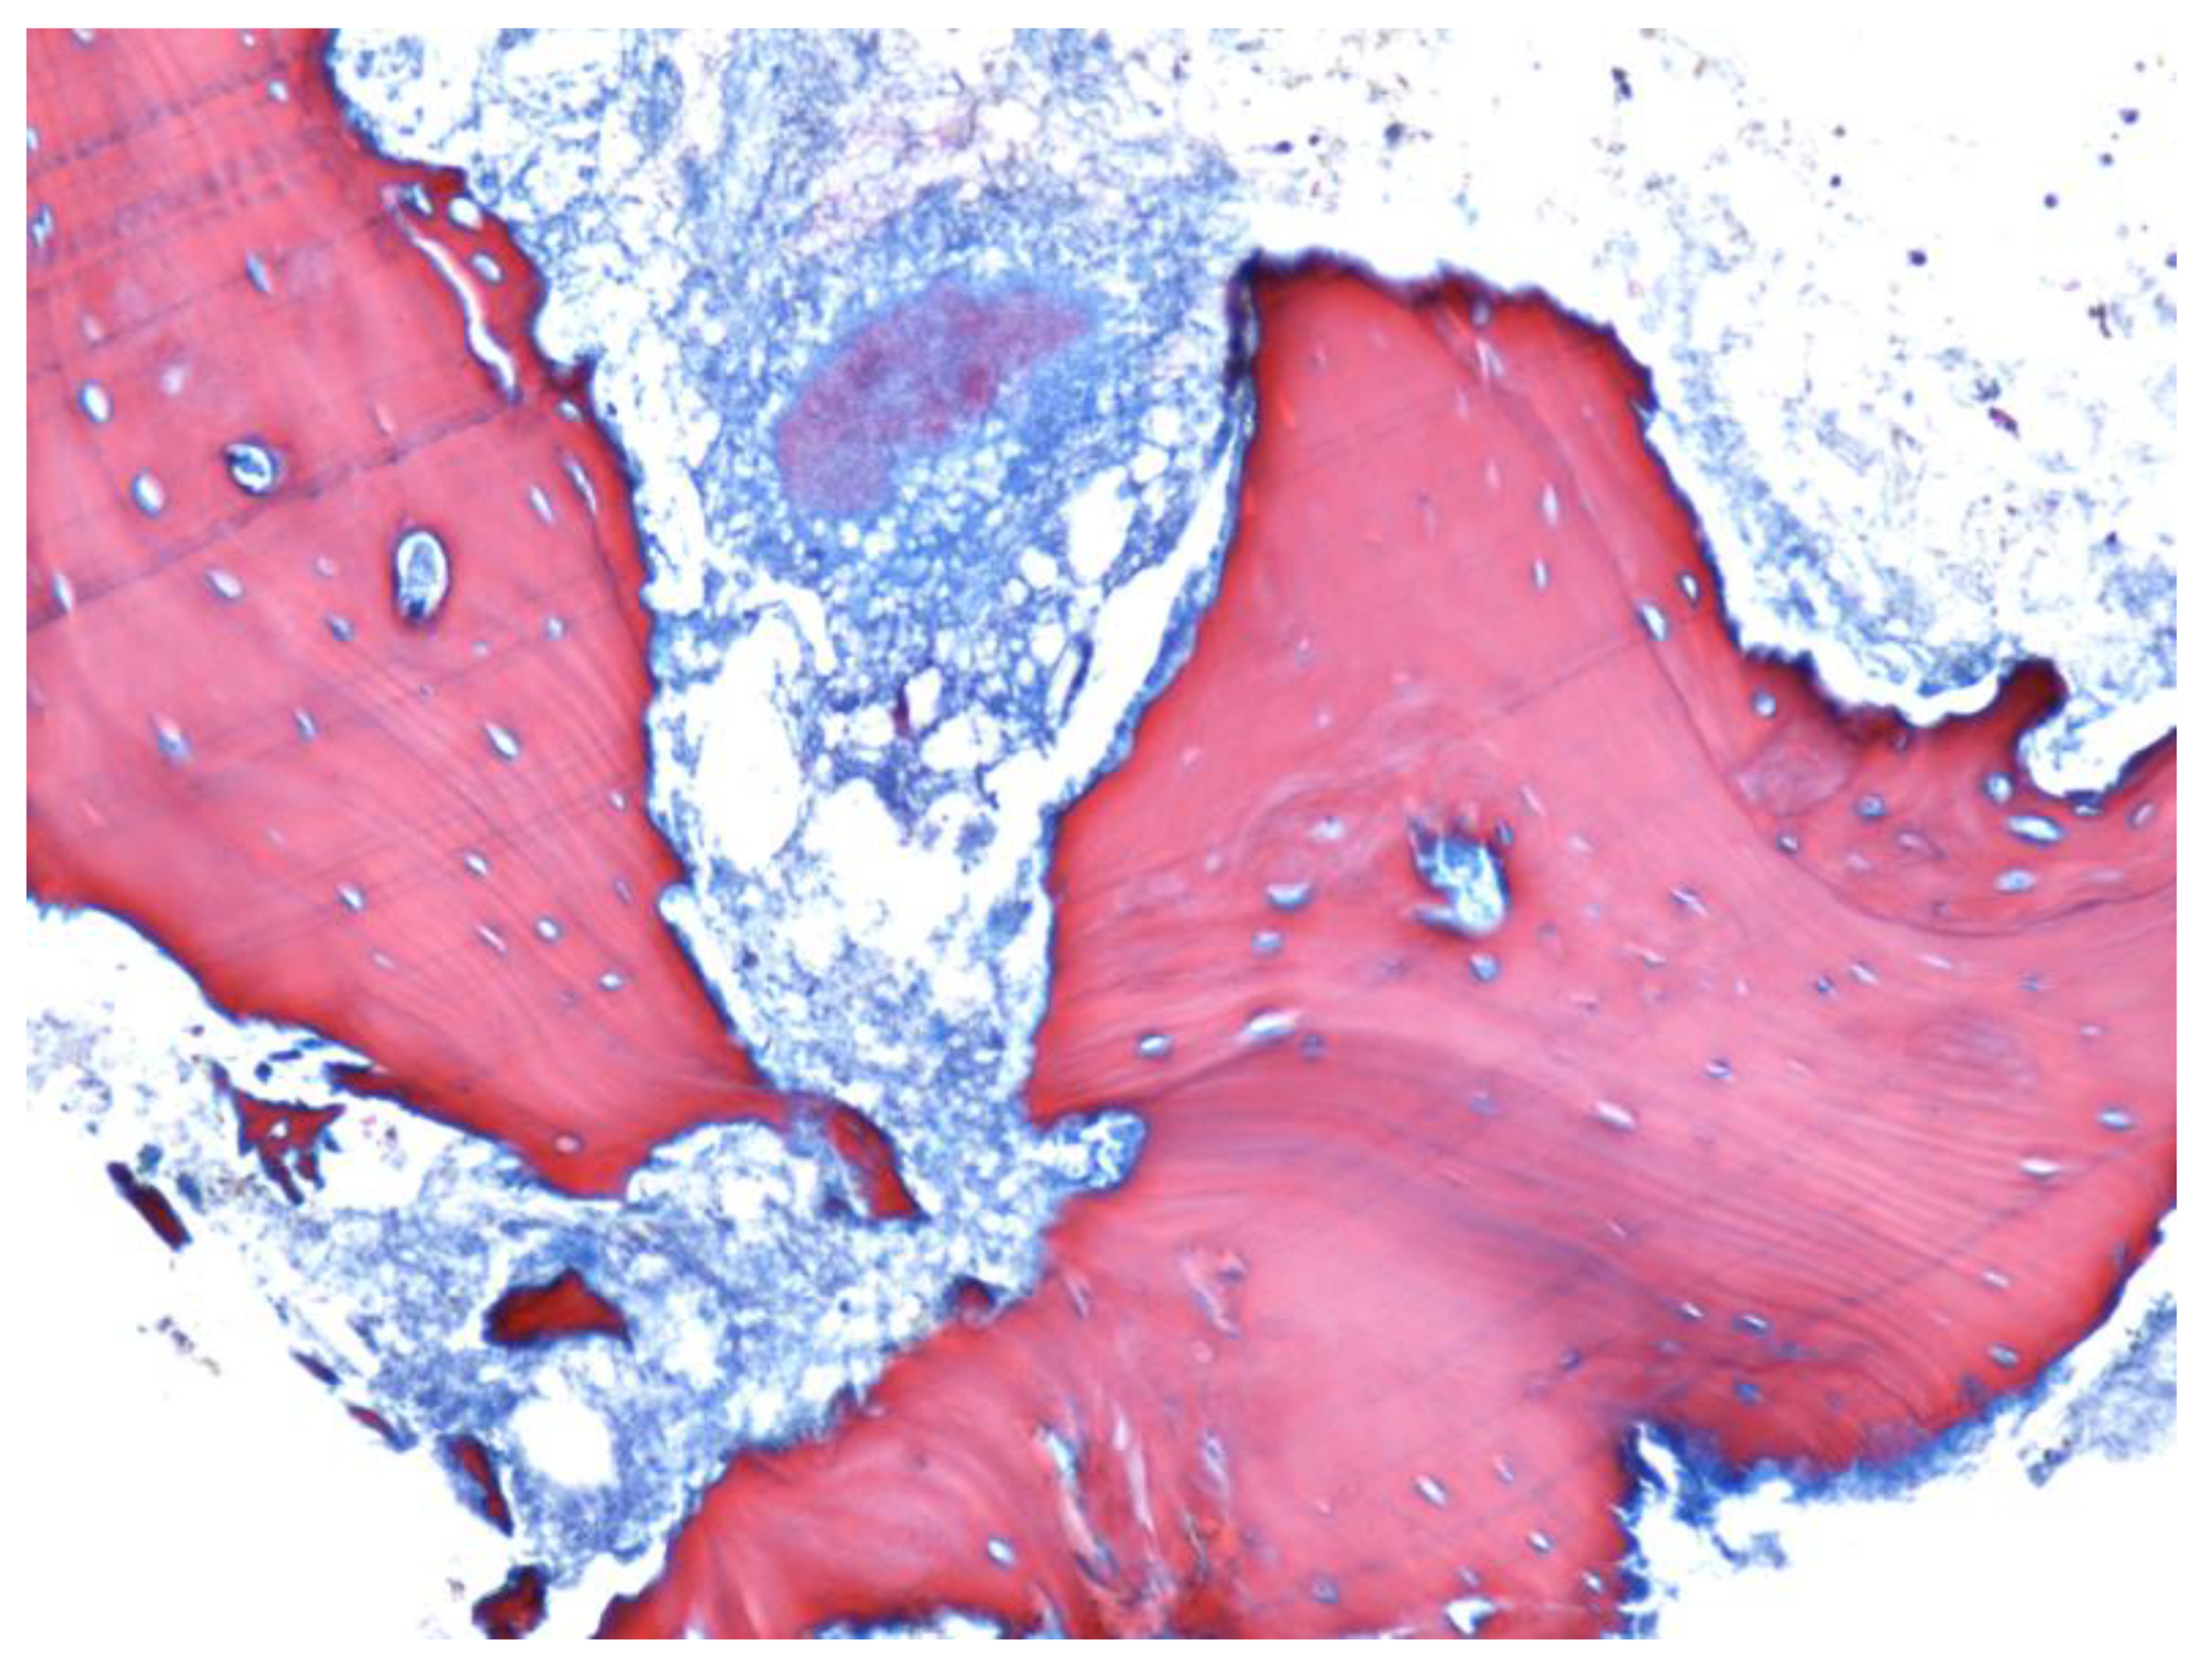

- Paparella, M.; Brandizzi, D.; Santini-Araujo, E.; Cabrini, R. Histopathological features of osteonecrosis of the jaw associated with bisphosphonates. Histopathology 2011, 60, 514–516. [Google Scholar] [CrossRef]

- Favia, G.; Pilolli, G.P.; Maiorano, E. Histologic and histomorphometric features of bisphosphonate-related osteonecrosis of the jaws: An analysis of 31 cases with confocal laser scanning microscopy. Bone 2009, 45, 406–413. [Google Scholar] [CrossRef] [PubMed]